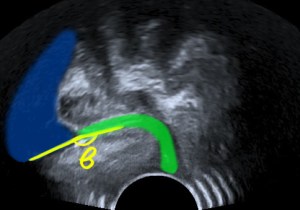

Open retrovesical angle (β). Green: urethra. Blue: bladder.